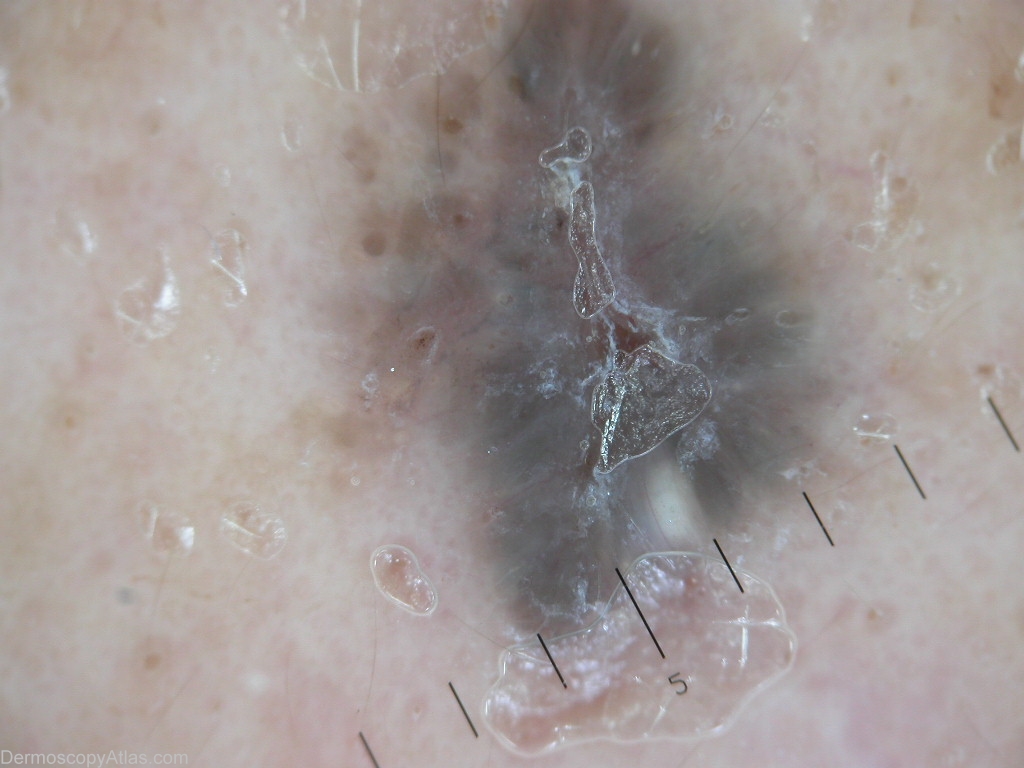

Diagnosis - Pigmented basal cell carcinoma

Diagnosis: Pigmented basal cell carcinoma